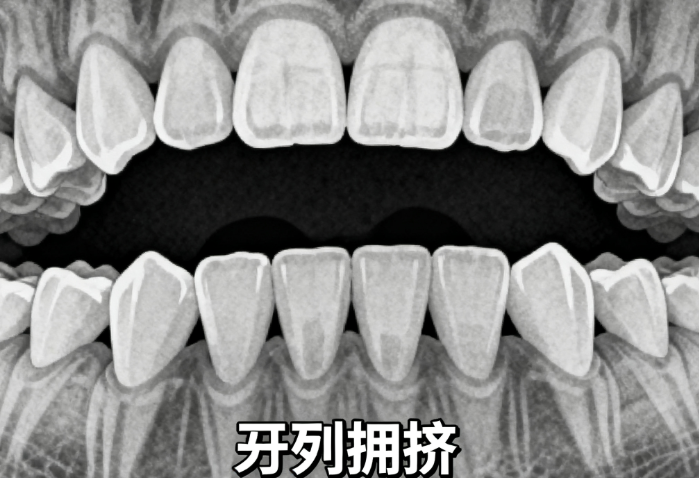

麻城作为湖北省重点县级市,口腔医疗资源相对集中,但患者在选择机构时仍需综合评估技术实力与性价比。以麻城阳光口腔为例,作为公办二级专科医院,其具备规范的诊疗流程与医疗保险资质,矫正价格(如金属自锁矫正8000元起)低于周边城市,且擅长处理复杂病例,如骨性龅牙、地包天等。而严氏口腔则以儿童早期干预为特色,3800元起的乳牙期矫正方案,配合70%的复诊率,成为家庭用户的选择。其他机构如时代口腔的3D口扫仪技术、安雅口腔的隐形矫正服务等,均在特定领域形成差异化优势。

阳光口腔、麻城市人民医院口腔科在骨性龅牙、牙槽骨改建等复杂项目上更具经验,适合中重度畸形患者。